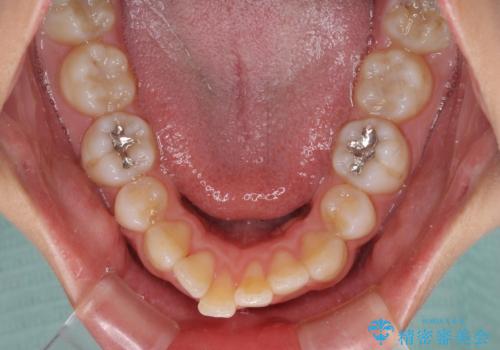

- 下顎前歯を中心に、以前行った矯正治療の後戻りが気になるとのことで来院された患者様です。

後戻りは軽度であったため、インビザライン・ライトにて治療を行うこととしました。

治療途中で出産をされたため、通院が困難となりましたが、インビザライン・ライトでの治療可能期限である2年以内に無事に治療を終えることができました。